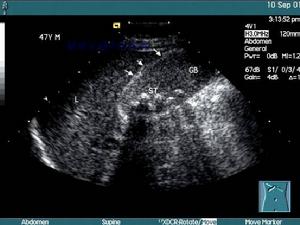

3.B型超聲檢查,膽囊增大,囊壁增厚,可能可看到結石的影像。

膽囊炎應與傳染性肝炎相鑑別,後者肝臟腫大,白細胞數可不增高且有肝功能減退現象。急性膽囊炎、膽管炎伴發腹膜炎時,應與其它原因所致腹膜為如闌尾炎、胰腺炎及消化道穿孔(如傷寒腸穿孔)等症相鑑別。除一般病史、體徵及X線檢查外,超音波可測知膽囊大小及囊壁是事粗糙增厚,腹腔穿刺檢查也有助於診斷。